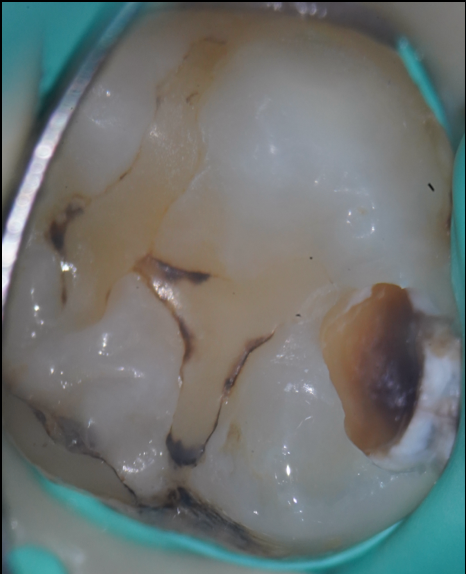

治療前

虫歯は細菌感染によって歯が溶けてしまう病気です。

治療では、虫歯に侵された象牙質(軟化象牙質)を丁寧に除去していきますが、それと同時に私たちが考えているのは、以下のようなことです。

まずは虫歯検知液を使用して、虫歯に侵された部分(軟化象牙質)を染色します。

しかし、一度の染色ではすべてが把握できないことが多く、少しずつ削っては染色→確認という作業を何度も繰り返します。

虫歯は健康な象牙質と隣接しているため、強く削りすぎると健康な歯まで失ってしまいます。

そこで当院では、細くよく切れるバーで“ブラッシングモーション(磨くような動き)”を行いながら、慎重に軟化象牙質を取り除いていきます。

虫歯が深く進行していると、治療中に歯髄(神経)に達することがあります。